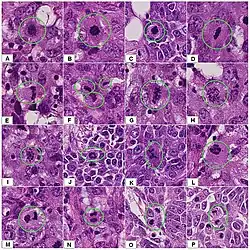

The Nottingham system[12] is recommended for breast cancer grading.[13] The Nottingham system is also called the Bloom–Richardson–Elston system (BRE),[14] or the Elston-Ellis modification[15] of the Scarff-Bloom-Richardson grading system.[16][17] It grades breast carcinomas by adding up scores for tubule formation, nuclear pleomorphism, and mitotic count, each of which is given 1 to 3 points. The scores for each of these three criteria are then added together to give an overall final score and corresponding grade. It is not applicable to medullary carcinomas which are histologically high-grade by definition, while being clinically low-grade if lymph nodes are negative.[18] It is also not applicable to metaplastic carcinomas.[19]

The grading criteria are as follows:

Tubule formation

This parameter assesses what percent of the tumor forms normal duct structures. In cancer, there is a breakdown of the mechanisms that cells use to attach to each other and communicate with each other, to form tissues such as ducts, so the tissue structures become less orderly.

Note: The overall appearance of the tumor has to be considered.[20]

- 1 point: tubular formation in more than 75% of the tumor (it may in addition be termed "majority of tumor")

- 2 points: tubular formation in 10 to 75% of the tumor ("moderate")

- 3 points: tubular formation in less than 10% of the tumor ("little or none")

Nuclear pleomorphism

This parameter assesses whether the cell nuclei are uniform like those in normal breast duct epithelial cells, or whether they are larger, darker, or irregular (pleomorphic). In cancer, the mechanisms that control genes and chromosomes in the nucleus break down, and irregular nuclei and pleomorphic changes are signs of abnormal cell reproduction.

Note: The cancer areas having cells with the greatest cellular abnormalities should be evaluated.

- 1 point: nuclei with minimal or mild variation in size and shape

- 2 points: nuclei with moderate variation in size and shape

- 3 points: nuclei with marked variation in size and shape

-

Ductal carcinoma with mild nuclear pleomorphism.

Ductal carcinoma with mild nuclear pleomorphism. -

.jpg) Invasive ductal carcinoma with moderate nuclear pleomorphism.

Invasive ductal carcinoma with moderate nuclear pleomorphism. -

Invasive lobular carcinoma with moderate nuclear pleomorphism.

Invasive lobular carcinoma with moderate nuclear pleomorphism. -

Invasive ductal carcinoma with marked nuclear pleomorphism.

Invasive ductal carcinoma with marked nuclear pleomorphism.

Mitotic count

This parameter assesses how many mitotic figures (dividing cells) the pathologist sees in 10x high power microscope field. One of the hallmarks of cancer is that cells divide uncontrollably. The more cells that are dividing, the worse the cancer.

Note: Mitotic figures are counted only at the periphery of the tumor, and counting should begin in the most mitotically active areas.